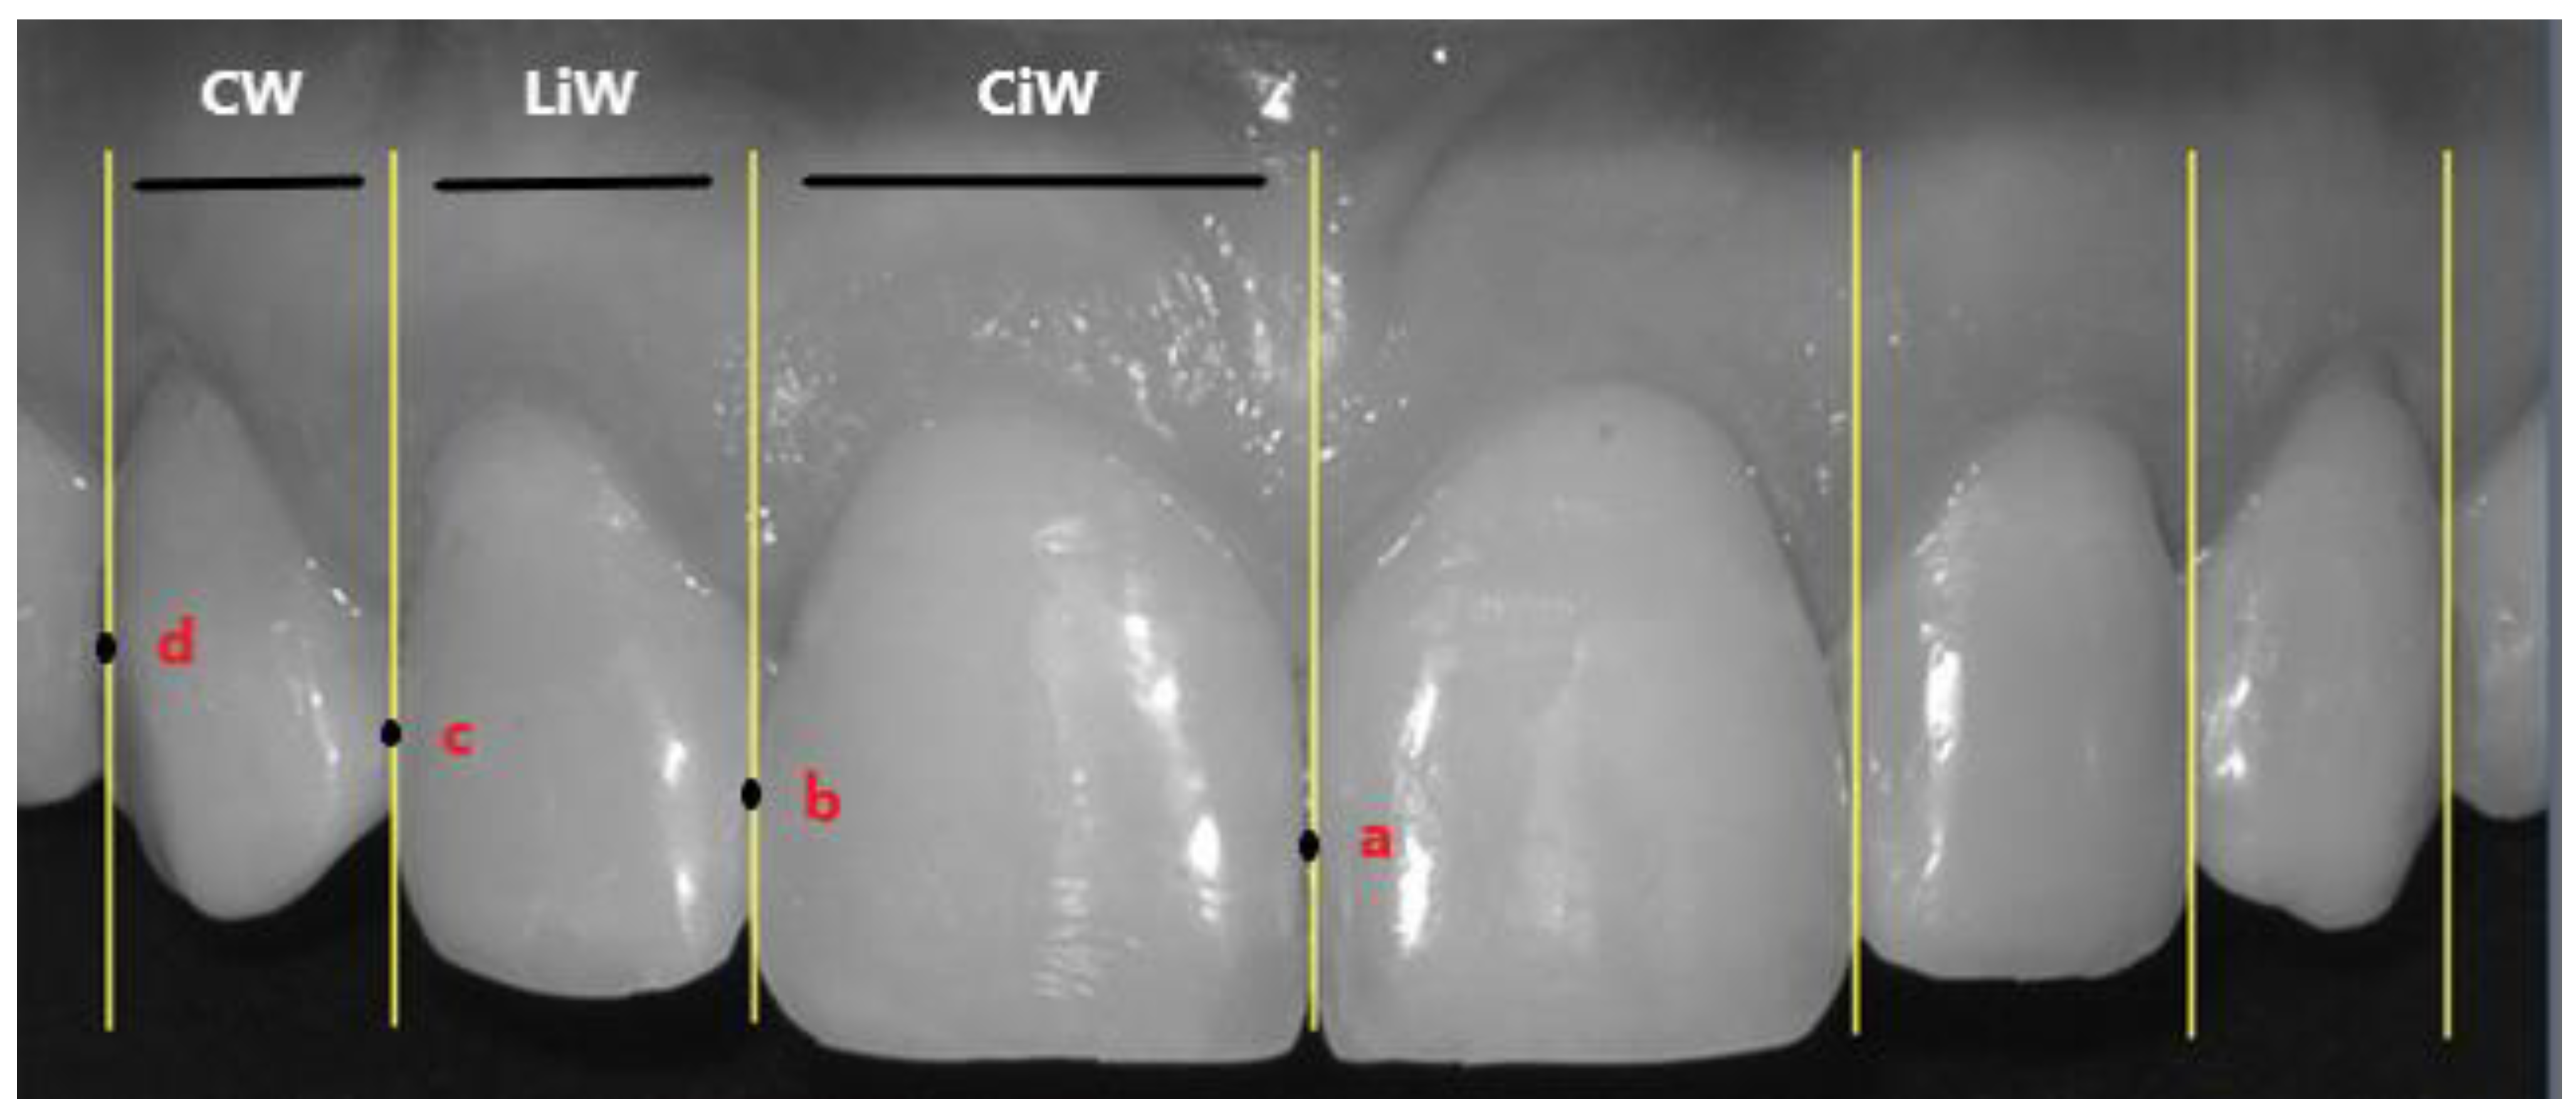

- Tangent lines to the two most distal points of the maximum equator of the central incisors (points a and b);

- Tangent lines to the two most distal points of the maximum equator of the lateral incisors (points b and c);

- Tangent lines to the most vestibular points of the visible surface of the canine (point d).

- According to Levin (GP theory), when considering the frontal view of a smile, the width of the upper lateral incisor (LiW) has a golden proportion to the width of the upper central incisor (CiW). Assuming that the LiW has a value of 1, the CiW should measure 1.618 and the upper canine (CW) should ideally assume a value of 0.6 [6,16] (Figure 2).

- According to Snow (GM theory), when considering the frontal view of a smile, the CiW should represent 25% of the distance between the reference external tangents to the upper canines (distance between point p1 and p2; Figure 3). According to this theory, the LiW represents 15% and the CW 10% [8] (Figure 3).